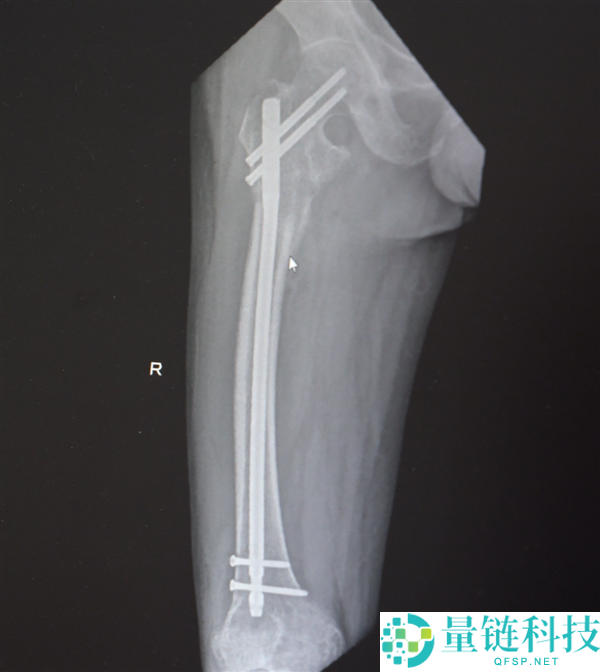

创伤性失血性休克、多发性肋骨骨折、肺部损伤、右侧肩胛骨粉碎骨折、右侧肱骨髁上开放粉碎性骨折、右股骨粗隆及股骨干粉碎性骨折、骨盆粉碎性骨折、腰椎横突多发骨折、腰骶柱神经损伤、臂丛神经损伤、胸腔积液、腹腔积液等。

经医生检查,张先生全身共有六处较大骨折部位,多为严重粉碎性骨折,全身骨折碎块达30多块!

部分手术后拍摄的影像